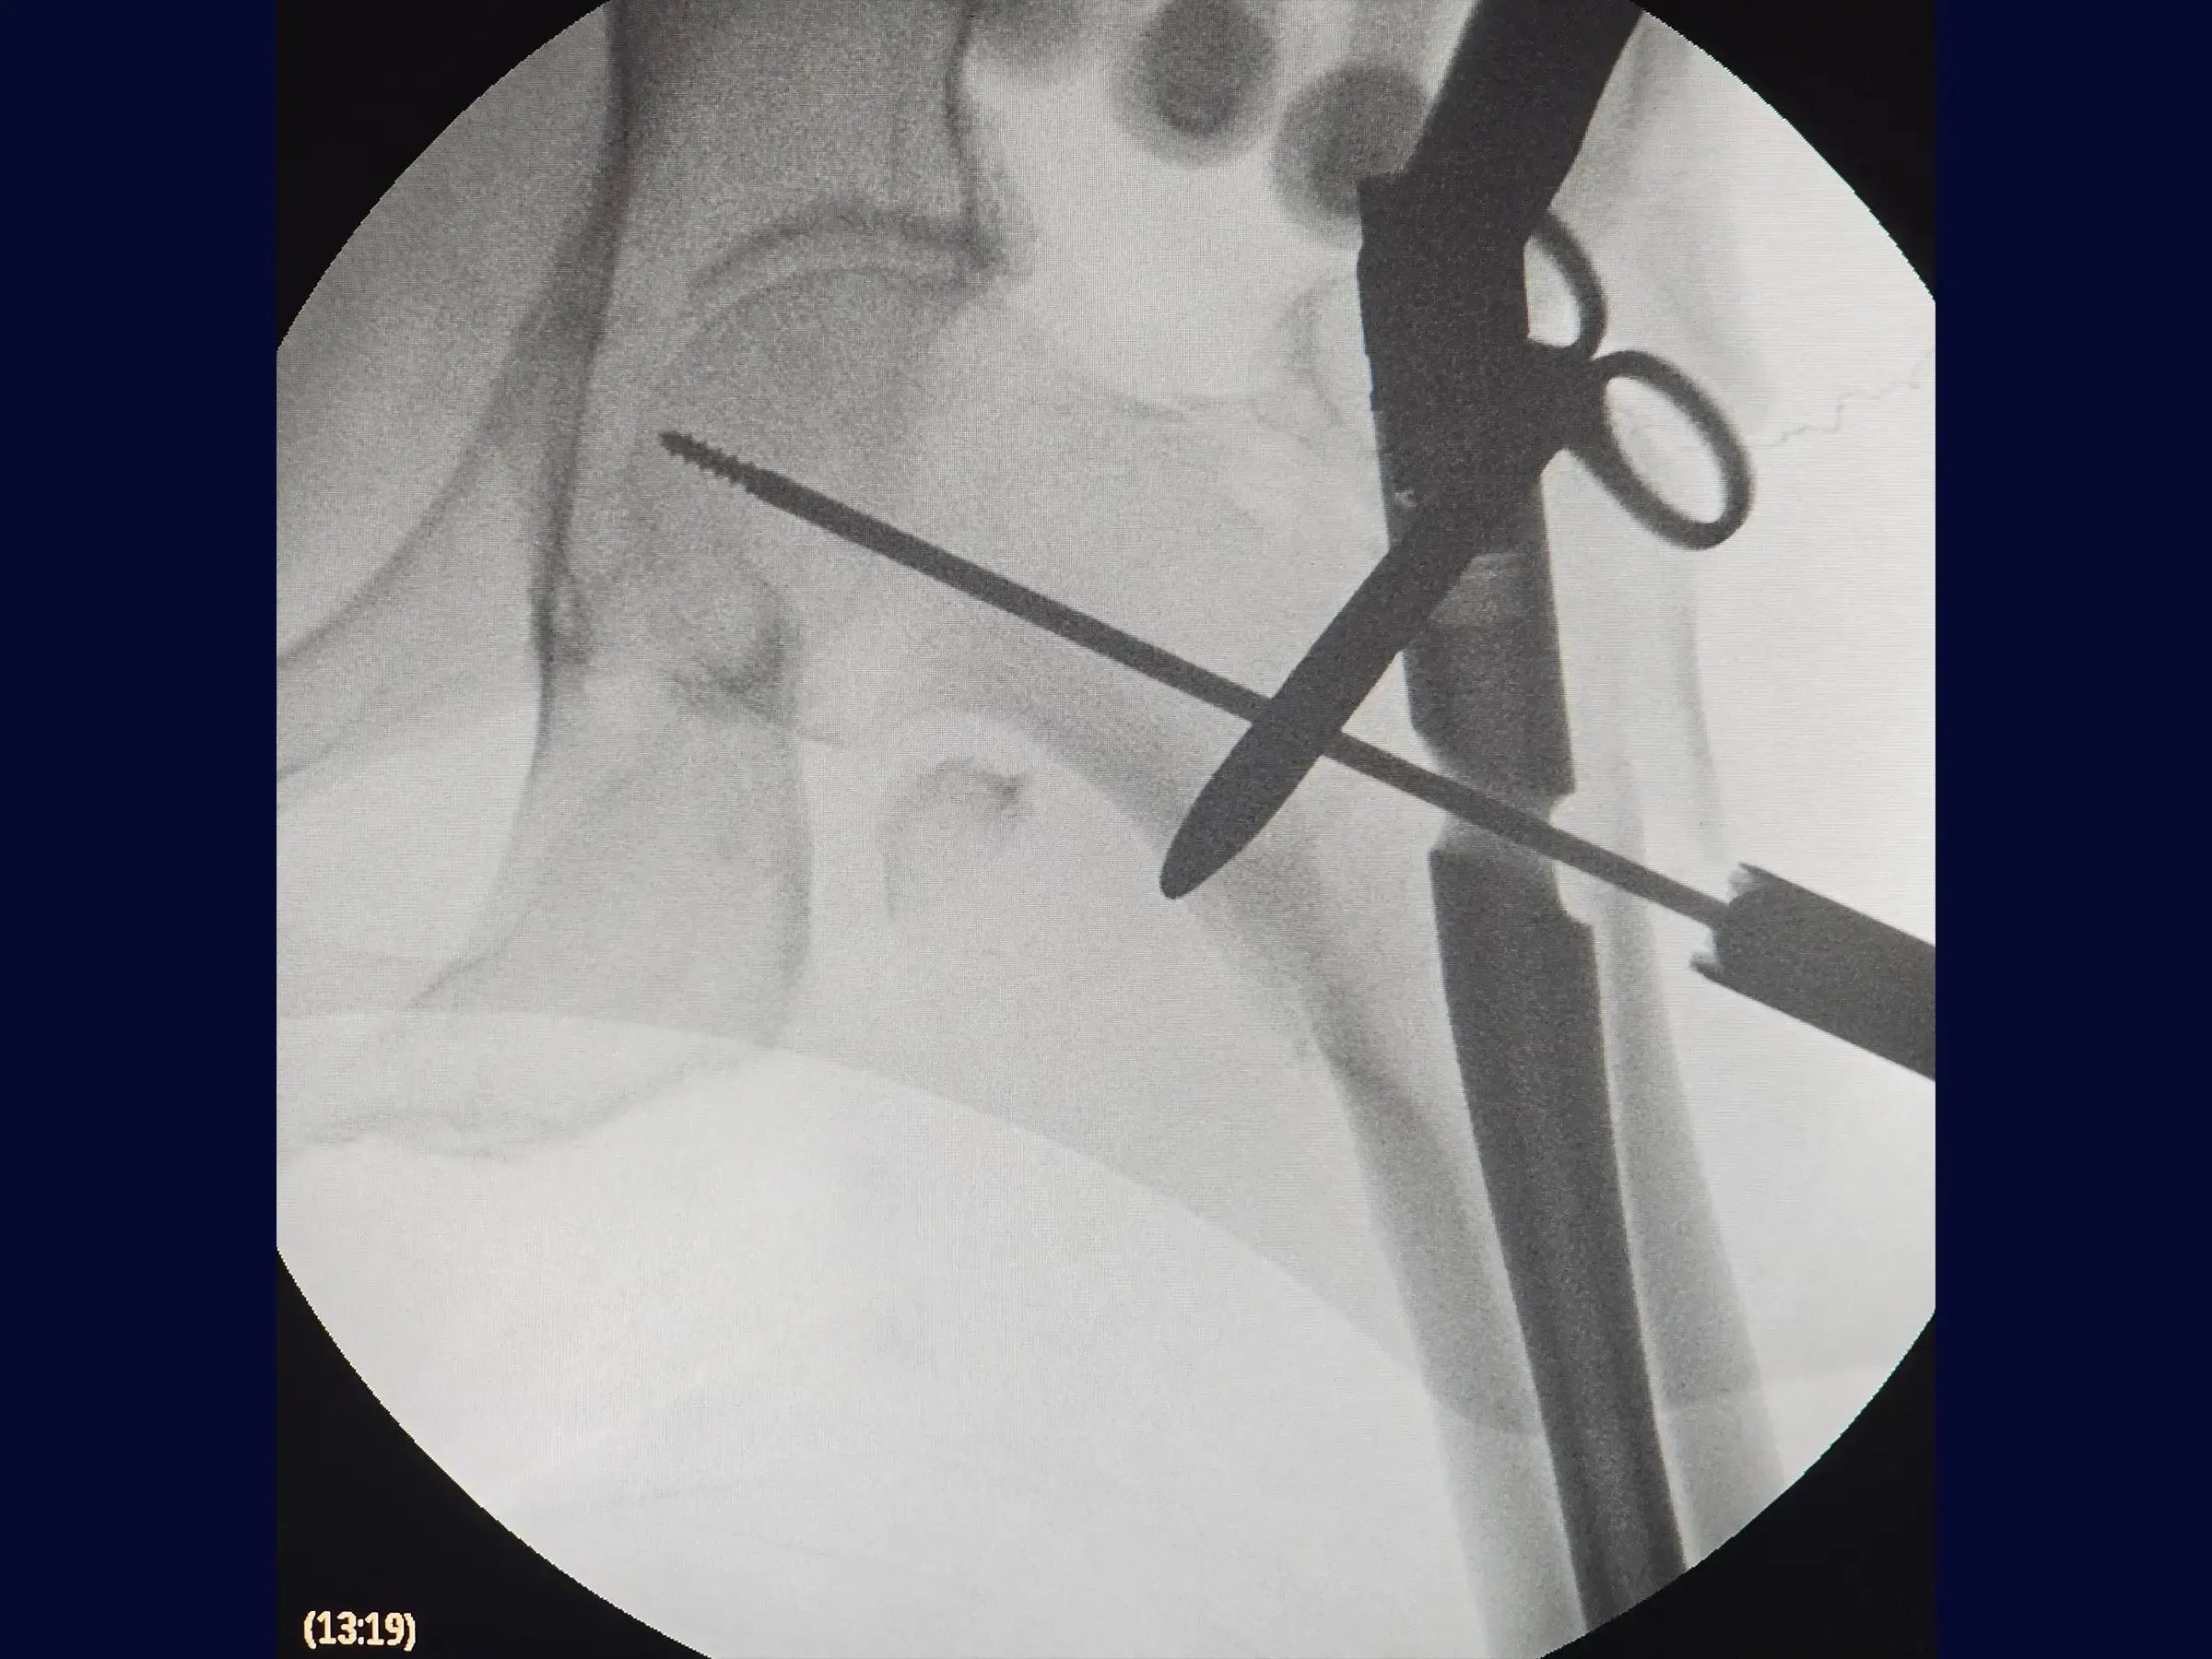

- Maniobra de reducción en balancín para fracturas impactadas y en valgo.

- Maniobra de reducción en balancín: Demostración de la técnica de reducción para fragmentos proximales valgos o impactados, incluida la creación de un miniportal seguro y la aplicación de la palanca para obtener y mantener la reducción anatómica con una manipulación mínima.

- Minimización del Acceso y Trauma Tisular: Estrategias para realizar el procedimiento con portales de entrada reducidos, promoviendo un carácter mínimamente invasivo y favoreciendo la movilidad temprana del paciente.